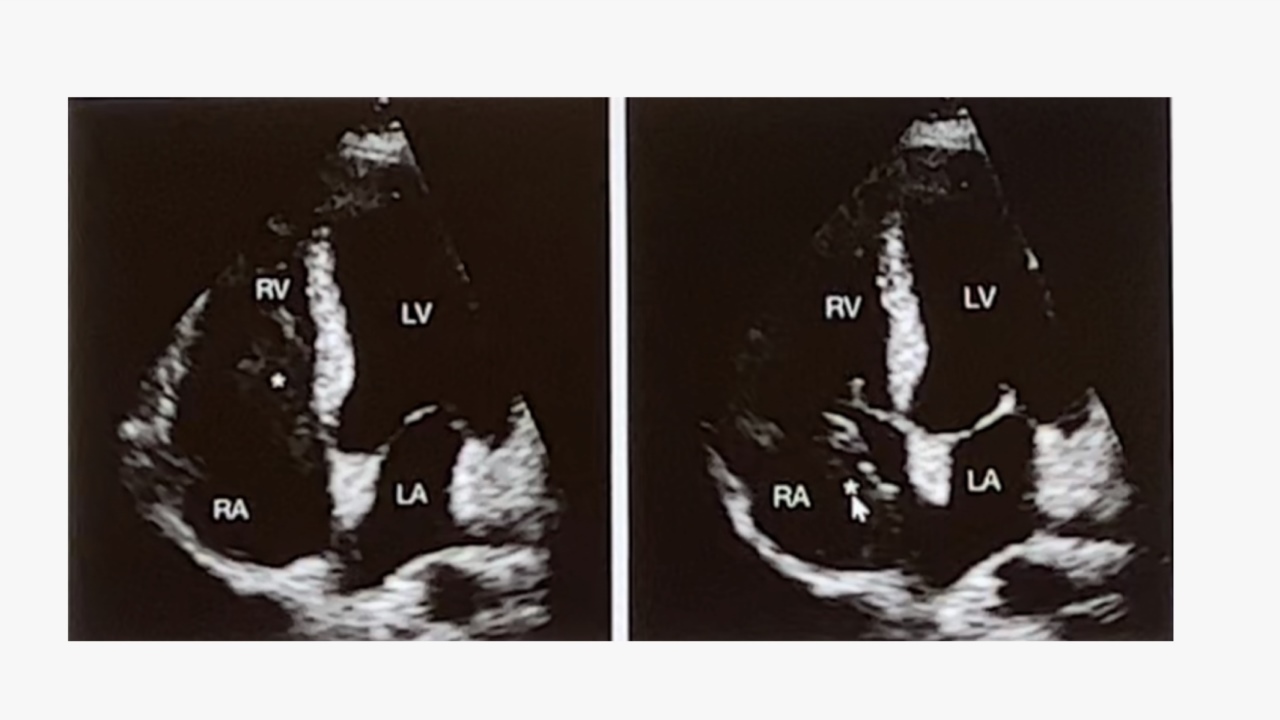

心脏超声:超声心动图检查时常发现右心房实性肿块,该肿块可随心脏收缩进入右心室,且与下腔静脉管壁无粘连。

术中经食道超声:可见右心房及右心室肿物,显示瘤栓延及右心房及右心室。